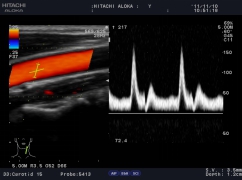

血流剖面圖

常規(guī)用多普勒方式測量血流速度只能測量某一點的速度,因此,測量血流量具有一定的局限性,日立阿洛卡推出的血流速度分布圖技術(shù)成功解決了此問題, 通過此技術(shù),醫(yī)生可以方便地得到整個血管剖面上的每一點的血流速度,從而準確計算出血管的流量。血流速度分布圖技術(shù)也可用于心排量的計算。

自動IMT測量

自動IMT檢測與手動測量相比提高了準確性,更方便,分辨率為0.01mm。系統(tǒng)可以自動描記并顯示結(jié)果和直方圖,直方圖可以更加直觀的觀察病變數(shù)據(jù),為動脈硬化的準確診斷提供了更為方便的工具。